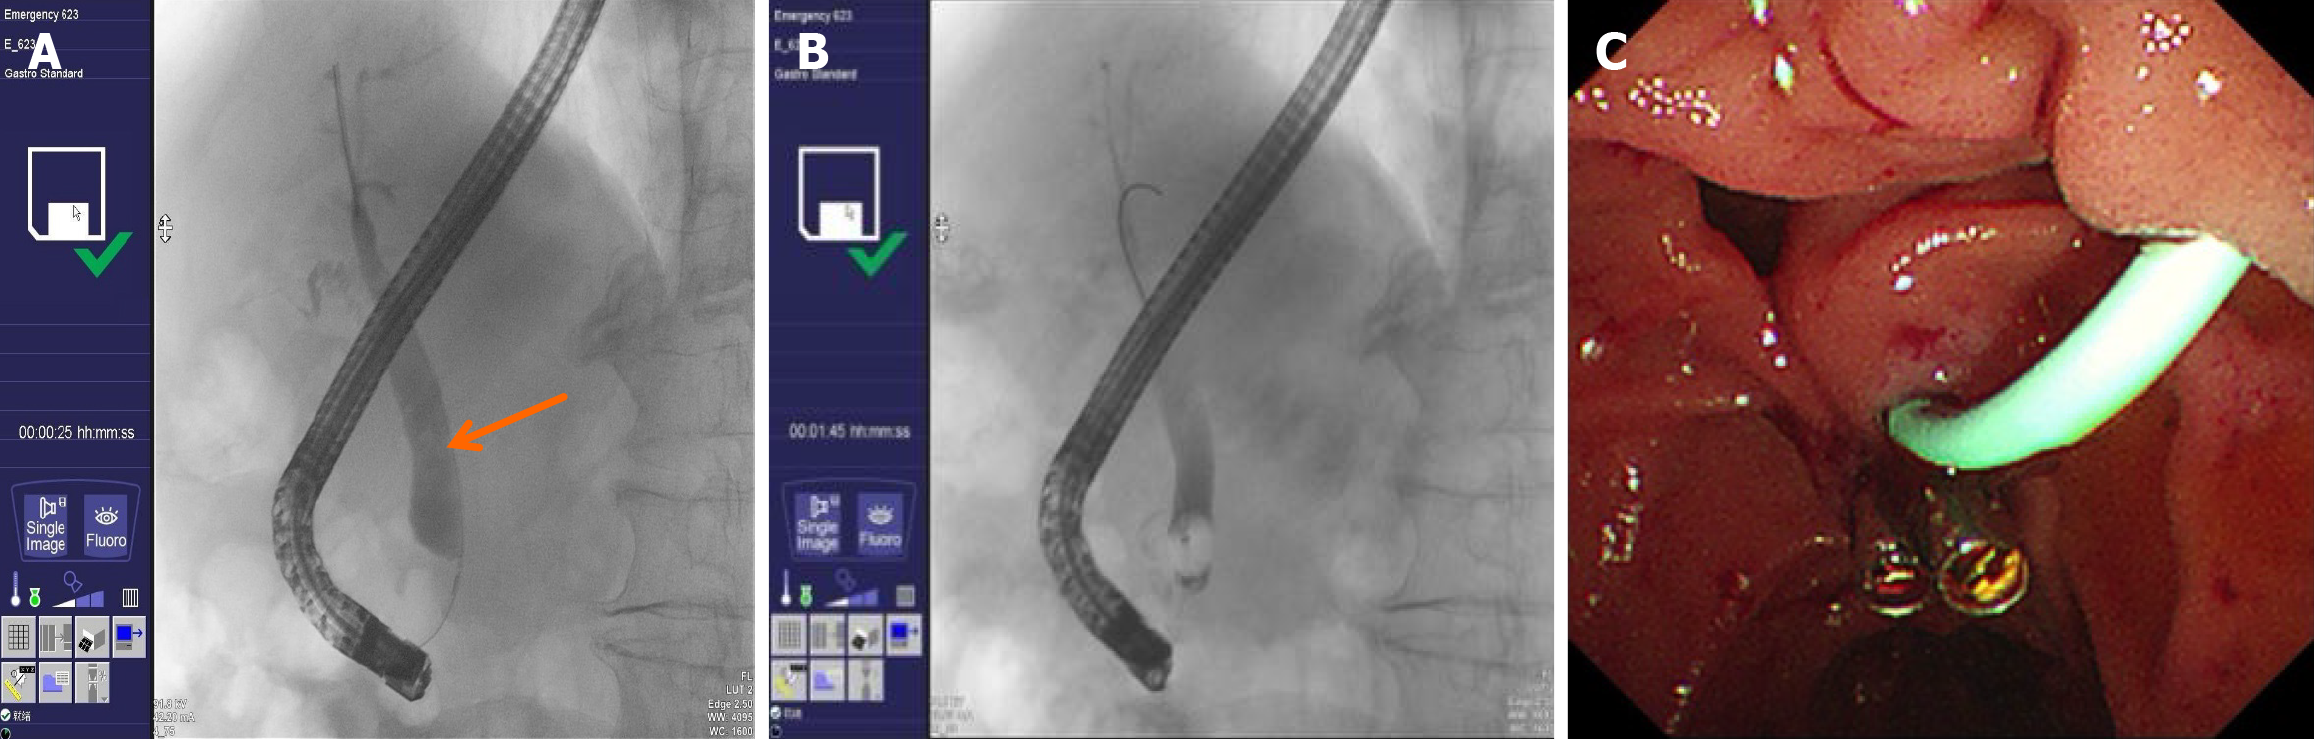

Figure 8 Classification of immunoglobulin G4-related sclerosing cholangitis biliary strictures[9].

Type 1 stricture confined to the intrapancreatic bile duct. Type 2 diffuse strictures involve both intrahepatic and extrahepatic bile ducts. Subtype 2a: Intrahepatic duct strictures with prestenotic dilation. Subtype 2b: Intrahepatic duct strictures without prestenotic dilation and with decreased biliary arborization. Type 3 combined strictures of the hilar bile ducts and the intrapancreatic bile duct. Type 4 isolated strictures of the hilar bile ducts. Arrow(s) indicate the location of the bile duct strictures. Citation: Naitoh I, Nakazawa T. Classification and Diagnostic Criteria for IgG4-Related Sclerosing Cholangitis. Gut Liver 2022; 16: 28-36. Copyright© Gut and Liver. This is an open-access article (Supplementary material).